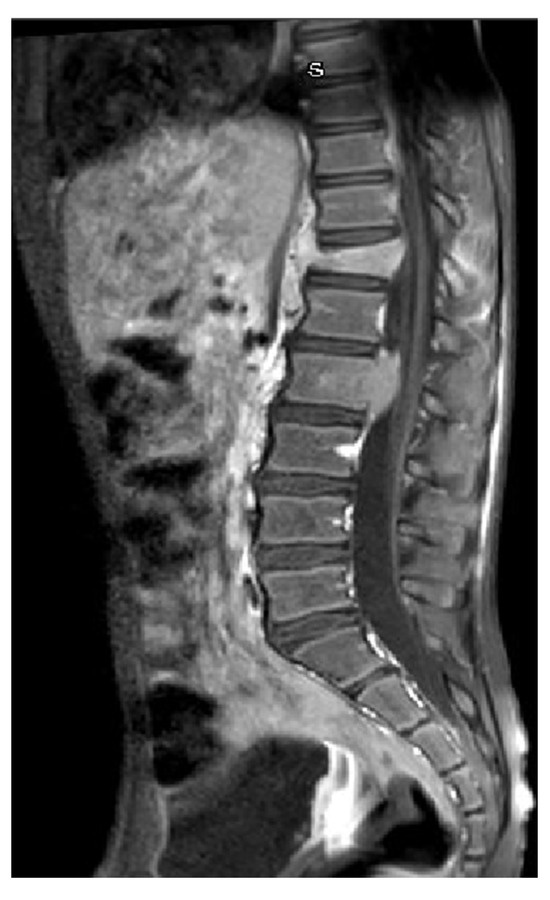

A previously healthy 9-year-old boy came to our attention for back pain, lasting more than 2 months, with no other symptoms; he had been treated with physiotherapy and anti-inflammatory drugs. On clinical examination, the boy was well-appearing, complaining of moderate back pain at the lumbar level. Complete blood count, lactate dehydrogenase, uric acid, C-reactive protein, and erythrocyte sedimentation rate were in the normal range. Spine magnetic resonance imaging (MRI) showed a signal alteration at the D12-L2 level (with a wedge-shaped D12 body) characterized by hypointensity at T1-weighted and hyperintensity at T2-weighted sequences; furthermore, an abnormal tissue involving medullary canal and neural foramina was appreciated at the D11-L1 level (Figure 1). Cerebral, thorax, and abdominal CT were of normal appearance. The boy underwent an open biopsy, and the histological diagnosis was ALCL, CD30+, ALK+, EMA+, perforin+, associated with numerous histiocytes CD68PGM1+. Positron emission tomography/computed tomography (PET-CT) showed high fluorodeoxyglucose (FDG) uptake at D11-L2 level, with spinal cord involvement. Lumbar puncture revealed the presence of 66 T-lymphoblasts/μL in the cerebrospinal fluid (CSF) and bone marrow aspirate was positive for NPM-ALK transcript, detected by qualitative RT-PCR. The patient was treated with six courses of chemotherapy according to the AIEOP LNH-97 protocol for ALCL, high-risk group, with CNS involvement (Table 1) [3]. MRD in bone marrow and peripheral blood was negative just after the first course of chemotherapy. PET-CT, performed after the second chemotherapy block, showed a complete metabolic response, confirmed also at the end of treatment. Spine MRI performed 2 weeks after stop-therapy demonstrated complete disappearance of both D12-L1 lesions and tissue proliferation in the D11-L1 region, with the persistence of mild signal alteration, without any contrast enhancement, at the L2 level only (Figure 2). During the follow-up, the boy was also monitored by the analysis of MRD in peripheral blood every month for the first three months, then every two months up to one year from the stop-therapy: NPM-ALK transcript was never detected. The patient is in clinical, radiological, and molecular remission at 12 months after the end of treatment.

Figure 2. Spine MRI after treatment: complete disappearance of both D12 lesion and tissue proliferation with persistence of mild signal alteration at L2 level.